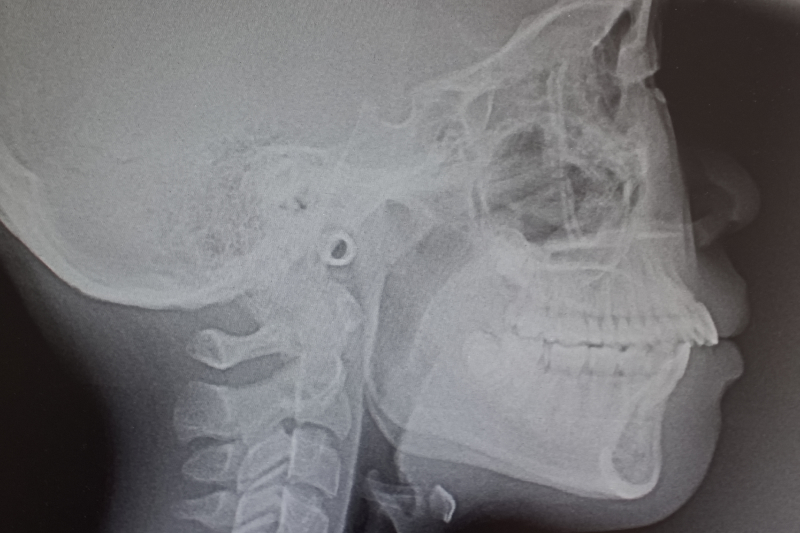

口腔内写真、顔貌写真、スキャニング、パノラマ/セファロ撮影、臨床情報の記入を行います。